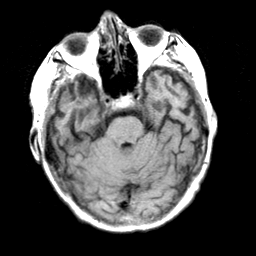

Pick's Disease, MR Study mr-t1 -- Slice #6

[Home][Help][Clinical] Slice 6